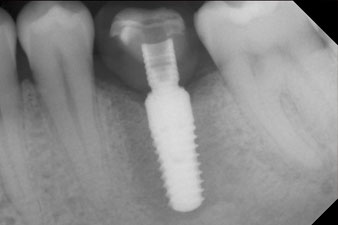

SmartPeg

Fig. 4: SmartPeg measuring posts screwed on to measure the implant stability quotients with the integrated W&H Osstell ISQ module.

The torque used for the machine-driven placement was 43 Ncm. In addition, after screwing a measuring post (SmartPeg) specially matched to the implant, the ISQ value was measured with the probe of the W&H Osstell ISQ module.

This module is an optional extra for the W&H Implantmed and is docked to the implantology motor (see Fig. 11). The dimensionless ISQ value immediately after insertion was 64 orovestibular and 68 mesiodistal (maximum value = 100).